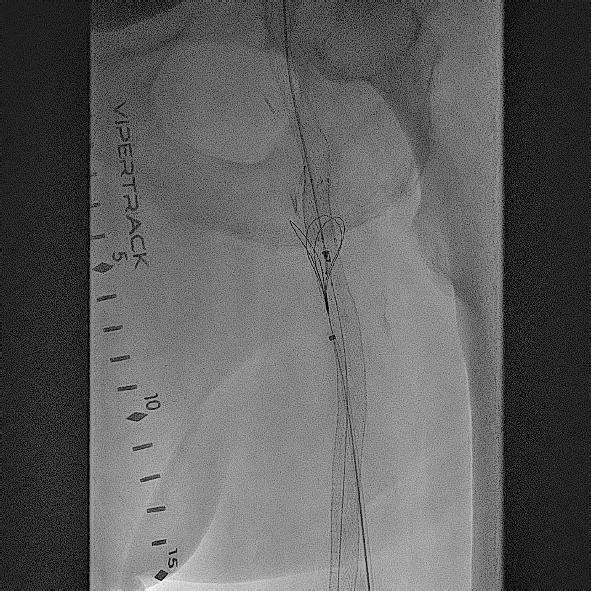

Based on his comorbidities, history of recurrent stenting of the left SFA, and an occlusion of the SFA over 200 cm, he was deemed to be an appropriate candidate for percutaneous transmural arterial bypass (PTAB). However, in order to establish long-term patency, we proceeded to gain posterior tibial artery access to identify a 3-vessel runoff (Figure 2). With this information, using the outline of the stents in left SFA and using a 0.018-in Glidewire Advantage (Terumo) and a 0.018-in Rubicon catheter (Boston Scientific), we were able to obtain access into the left profunda femoral artery (Figure 3). Despite multiple-balloon angioplasty, the recoil within the left common femoral artery (CFA) left little option but to place a 7.0-mm Eluvia stent (Boston Scientific), which was overlapped with the proximal stent in the left SFA (the profunda femoral artery was patent after balloon angioplasty; Figure 4).